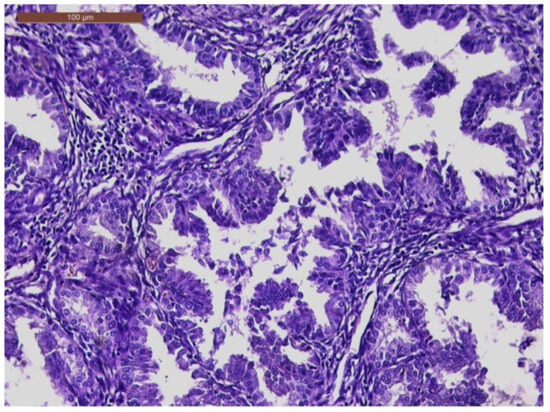

An MRI was performed that described a solid expansive formation, well delimited, with an inhomogeneous structure, with small cystic areas and an intense contrast socket. The mass was located in the vagina, apparently originating from the cervical level, with which it communicates over a distance of 4 mm, presenting the overall dimensions of 44/47/47 mm. The uterine body, the ovaries, and the pelvic organs were within normal limits. No images of pelvic adenopathies were revealed (Figure 2).

Figure 4. Endometrial glands with lymphoid follicles and associated smooth muscle fibers (HE × 10).